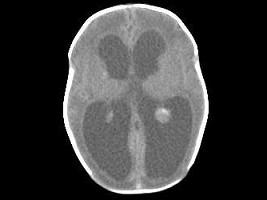

问题 1岁,女,头颅呈球状,颅骨透光试验阳性,请结合CT图像选择最可能诊断 ( )

选项 A、先天性脑积水 B、外部性脑积水 C、慢性双侧性巨大硬膜下血肿 D、水瘤 E、脑严重缺血

答案 A